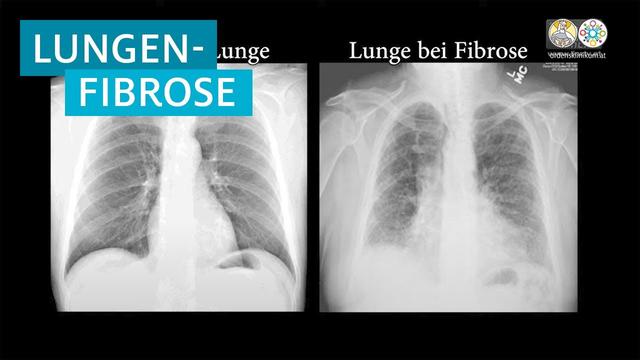

Mit einer Messung des Lungenvolumens und einer Blutgasanalyse beurteilen wir die Lungenfunktion. Die Röntgenaufnahme der Lunge und die Thorax-Computertomografie ergeben Bilder der Lungensstruktur. Sind die Untersuchungen unauffällig, können wir eine Lungenfibrose ausschließen. Gibt es auffällige Veränderungen, ist es für die Behandlung wichtig, die Ursachen zu klären.

Mit Hilfe von Lungenvolumenmessungen und Blutgasanalysen kann die Lungenfunktion beurteilt werden. Röntgenaufnahmen oder Computertomografien des Thorax liefern Bilder von der Struktur der Lunge. Sind diese Untersuchungen unauffällig, kann eine Lungenfibrose ausgeschlossen werden. Bei auffälligen Veränderungen ist es wichtig, die Ursachen zu klären, wofür eine Bronchoskopie (Lungenspiegelung) durchgeführt wird. Dabei wird unter Narkose ein flexibler Katheter mit einer Mini-Kamera durch den Mund in die Atemwege geschoben, um die Schleimhäute der Luftröhre und Bronchien zu untersuchen. Möglicherweise werden Gewebeproben entnommen, die im Labor feingeweblich untersucht werden.

– Röntgenaufnahme der Lunge: Eine Röntgenaufnahme kann erste Hinweise auf eine Lungenfibrose liefern. Dabei werden Bilder der Lungensstruktur erstellt.

– Thorax-Computertomografie (CT): Die CT ermöglicht detailliertere Aufnahmen der Lunge und kann spezifische Anzeichen für eine Fibrose zeigen. Sie wird oft in Kombination mit einer Perfusions-Szintigraphie durchgeführt, um die Durchblutung der betroffenen Areale zu beurteilen.